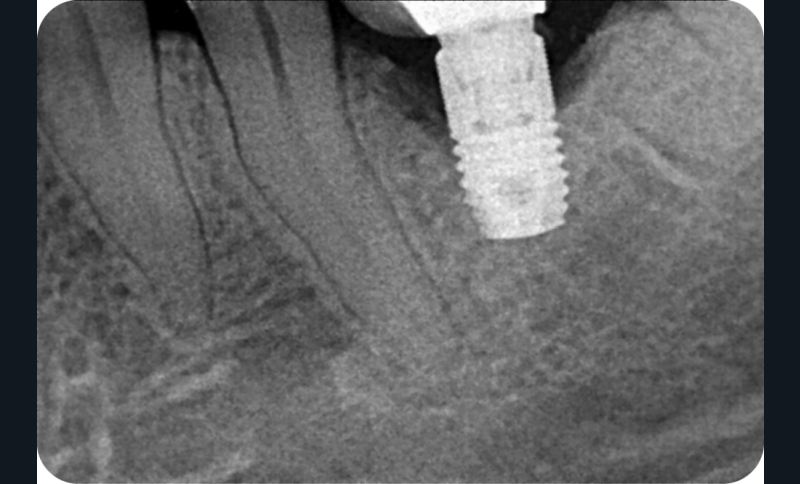

Conclusion

Chez ce patient, le traitement de la péri-implantite a comporté une chirurgie associant décontamination électrolytique de la surface implantaire, régénération osseuse guidée et enfouissement de l’implant. Le résultat à 2 ans est très moyen au vu du pourcentage de régénération osseuse obtenu. Comment peut-on prévoir un tel résultat alors que l’on a suivi les recommandations à la lettre, que l’on a utilisé les dernières technologies de décontamination, que l’on y a mis tous les moyens, que le patient est en bonne santé générale et qu’il vient en plus régulièrement aux séances de thérapeutique de soutien ? Le succès du traitement des péri-implantites n’est pas simple à obtenir, surtout quand un élément clé est compromis… la maintenance personnelle ! En effet le succès n’est possible que si le contrôle de plaque quotidien est optimal et, ici, ça n’était pas le cas. Le patient se brossait certes les dents, mais ne passait pas quotidiennement les brossettes, ce qui…